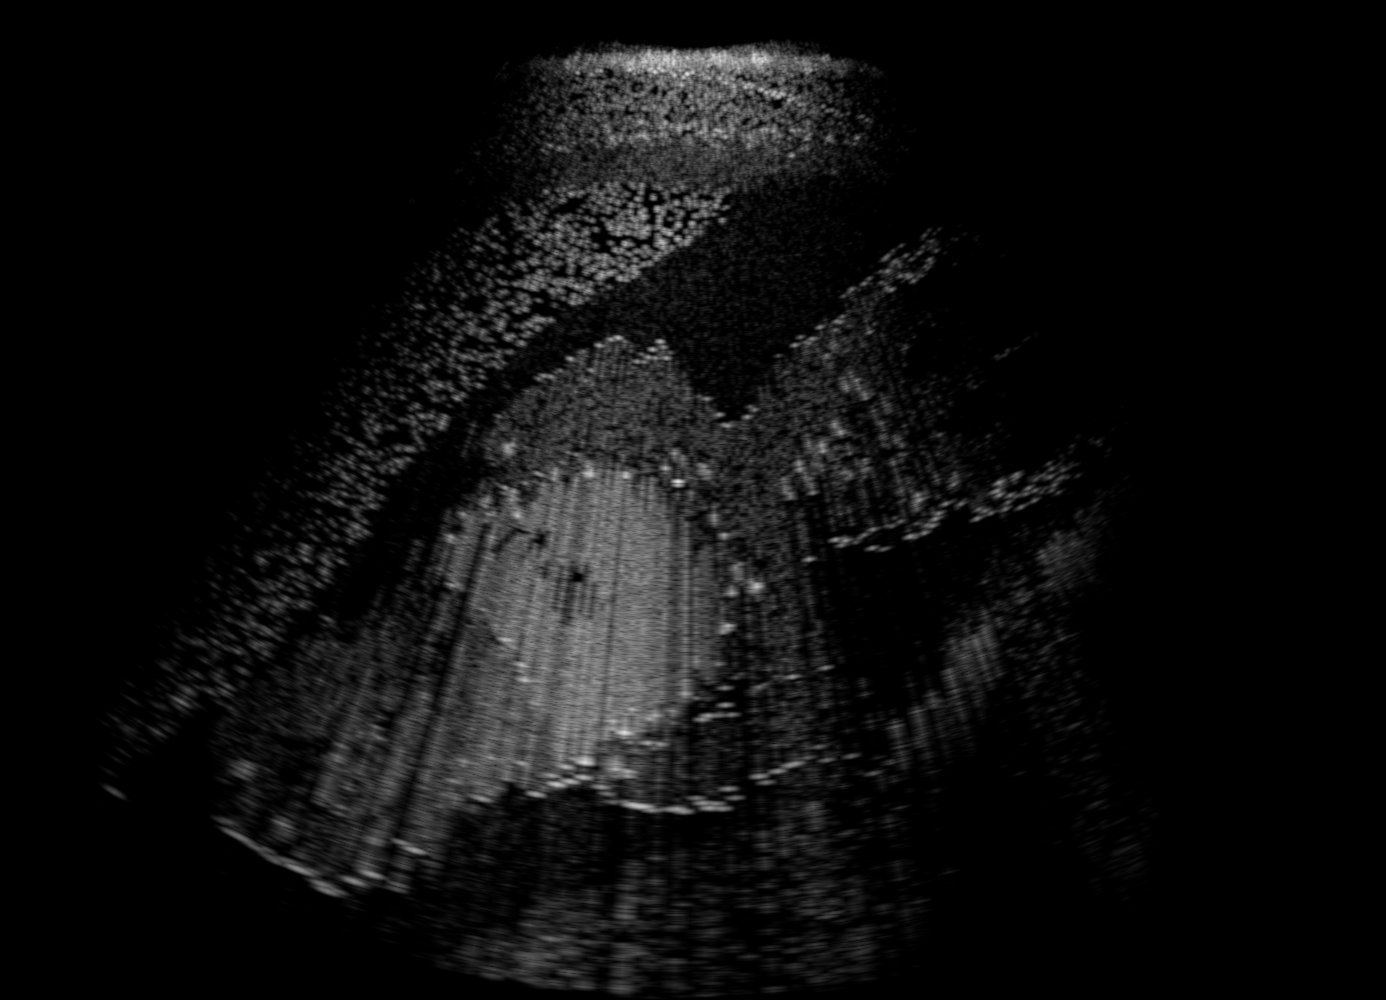

3.1 Full field-of-view Images

Above image translation has been demonstrated on patches. For the entire field-of-view (FoV) US images, patch fusion from image translation of non-overlapping patches would cause artifacts at image seams. Averaging overlapping patches, on the other hand, would blur the essential US texture. Although seamless tiling of US images is possible using graphical models [3], this requires prohibitively long computation time. Herein, we instead directly apply our trained generator on full FoV low-quality images, since the generator is fully convolutional and thus can operate on images of arbitrary size. Fig. 4 shows two examples of translated images by L2HMS and L2HMSA, demonstrating direct inference on full FoV images. While anatomical structures are well preserved and the effect of attenuation integral map is apparent, speckle texture appearance is seen to degrade slightly especially in the top image regions, where the ultrasound texture looking particularly different due to focusing difference and near-field effects.

(a) Input

(b) L2HM

(c) L2HMS

(d) L2HMSA

(e) Target